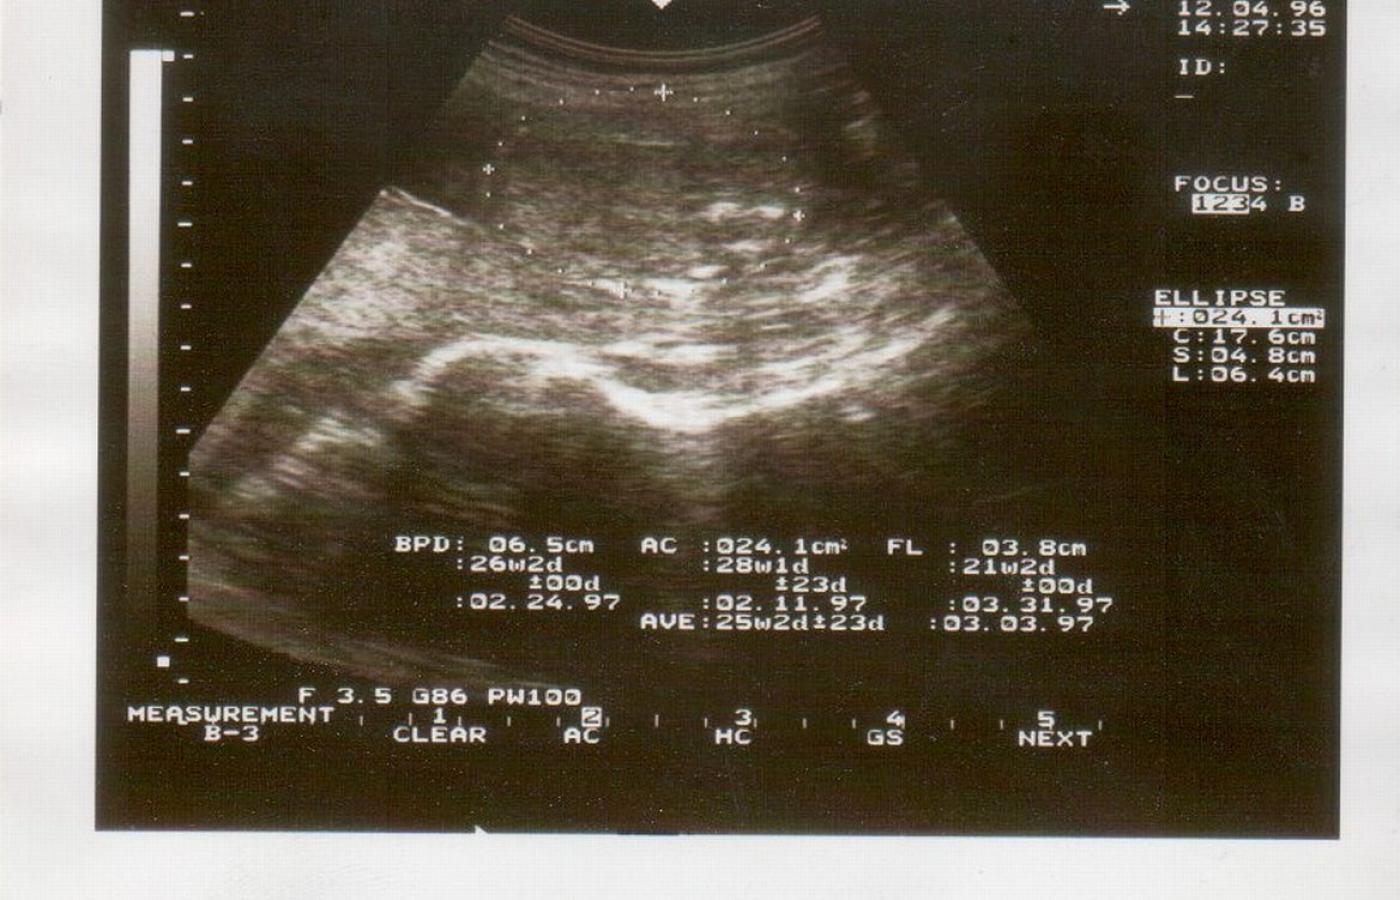

W Polsce i w większości krajów Europy badanie płodu w kierunku wykrycia nieprawidłowej liczby chromosomów obejmuje przede wszystkim, między 11 a 14 tygodniem ciąży, badanie usg. wraz z badaniem biochemicznym, nazywanym testem PAPP-A. Gdy są ku temu wskazania, ocenia się również kariotyp (czyli zestaw chromosomów u dziecka), co wymaga wykonania wspomnianej amniopunkcji. – Już dawno zauważono, że wiek ciężarnej powyżej 35 lat jest słabym czynnikiem determinującym wystąpienie zaburzeń chromosomowych u płodu, niemniej specjalistyczna ultrasonografia oraz test PAPP-A są nadal szczególnie zalecane w tej grupie – przyznaje dr Węgrzyn.

NFZ nie chce refundować tych badań ciężarnym poniżej 35 roku życia, mimo że to one rodzą zdecydowaną większość dzieci z zespołem Downa. Z tego powodu około 12 tygodnia wszystkie ciężarne powinny wykonać usg. pozwalające ocenić parametry rozwoju płodu – w tym także te, które nasuwają podejrzenie wady genetycznej (chodzi tu zwłaszcza o tzw. przezierność karku, będącą markerem typowym dla zespołu Downa) oraz test PAPP-A. – Jeśli usg. wykrywa nieprawidłowości, należy wykonać badanie inwazyjne – radzi dr Beata Nowakowska. – Ale są kobiety starsze, które decydują się na amniopunkcję na wszelki wypadek, aby upewnić się, czy z dzieckiem wszystko w porządku. U nich nieinwazyjne badanie może w dużo bezpieczniejszy sposób dać odpowiedź w kwestii najczęstszych wad genetycznych.